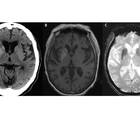

Early Clinically Unsuspected Alzheimer’s Disease

Georgette A. Khoury, MSN, APRN-BC; Ira GoodmanGeorgette A. Khoury, MSN, APRN-BC; Ira Goodman - Imaging & Testing